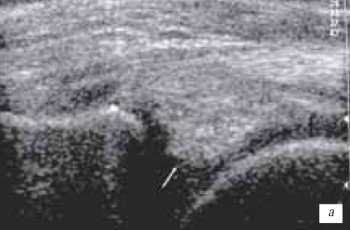

Наиболее часто синовиты возникают в супрапателлярном пространстве (верхний заворот). Супрапателлярная сумка является самой большой в человечеством организме и распространяется на 6 см вверх проксимальнее верхнего полюса надколенника. Любые воздействия на коленный сустав (травматические, воспалительные, подагрические) приводят к возникновение повышенного количества синовиальной жидкости в верхнем завороте сустава (рис. 1 а, б).

а) Выраженный синовит коленного сустава с наличием утолщенной, с краевыми разрастаниями синовиальной оболочки (стрелка).

б) Затяжной хронический синовит с наличием утолщенной синовиальной оболочкой и участками склероза (стрелка).